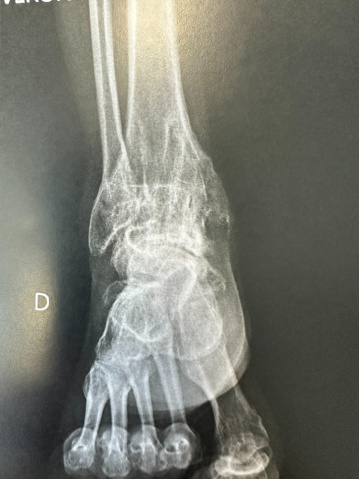

L’articulation de la cheville est constituée du tibia et de la fibula, d’une part et du talus, d’autre part. Une usure du cartilage entre ces os aboutit à de l’arthrose.

L’arthrose peut être primitive ou secondaire (séquelle d’une fracture de cheville, d’entorses, nécrose, etc.).

Dans les formes sévères, l’intervention consiste à supprimer la mobilité qui persiste entre tibia/péroné et talus, puisque celle-ci est source de douleur. Une arthrodèse (blocage de l’articulation) est donc pratiquée.